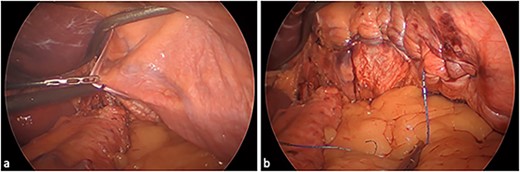

We therefore performed laparoscopic Roux-en-Y gastric bypass (RYGB), hiatal repair, and diaphragmatic plication. The technique involved crural dissection, division of the phreno-oesophageal ligament, and then opening of the left pleura for left-sided thoracic insufflation. The primed left diaphragm was then plicated medial to lateral using a non-absorbable barbed suture (Fig. 2; see Video 2). Hiatal repair was performed with posterior cruroplasty and oesophagopexy. A transected lesser curve gastric pouch was created by dividing the previous sleeve at the angularis. A 100/60 cm antecolic Roux/biliopancreatic limb configuration was constructed via hand-sewn gastroenterostomy and stapled enteroenterostomy. Finally, the internal hernia defects were closed. No drains were inserted.

Eventrated left hemidiaphragm: (a) unrepaired and (b) post medial-to-lateral plication.